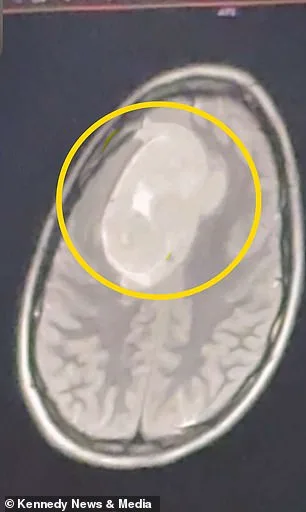

The first doctor's dismissal lingered in her mind, but Keating persisted. During a Christmas break visit home, she sought a second opinion. This time, an MRI revealed the truth: a tumor roughly the size of a tennis ball pressing against her left frontal cortex. The scan, taken in January 2026, showed a mass that had been growing for years, silently eroding the part of her brain responsible for executive function, motor control, and language. Doctors urged immediate action. 'They told me to go to the emergency room right away,' she said, her voice trembling with the memory of that moment. 'I was stunned. That was the last thing I would have expected.'

The tumor was benign, but its location made it dangerous. Left untreated, it could have caused irreversible damage—personality shifts, cognitive decline, or loss of motor skills. Keating underwent a six-hour craniotomy, a procedure where part of her skull was temporarily removed to extract the mass. 'I was scared and worried about the surgery,' she admitted. 'I didn't know coming out of it how I would act... or if there would be neurological effects.'